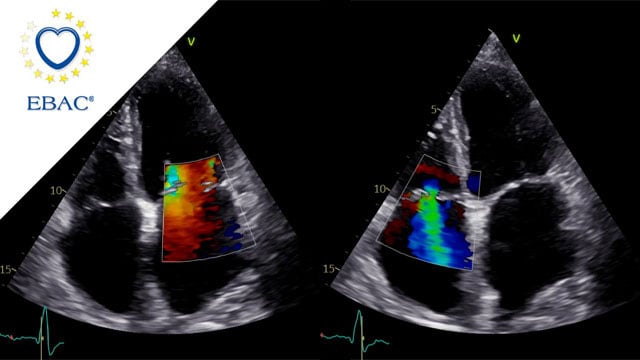

A simple maneuver to track the wire during a transseptal mitral valve-in-valve procedure

05 Nov 2025

Advancing a transcatheter heart valve through the septostomy can be tricky, with the wire sometimes prolapsing into the left atrium.

This step-by-step tutorial demonstrates a simple yet effective maneuver that allows smooth, controlled navigation from the right atrium to the mitral position, ensuring precise valve deployment.